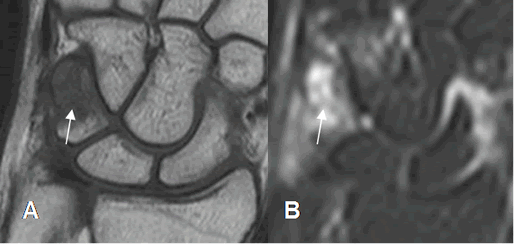

Fig 43. Fractura del piramidal.

A: RM coronal en T1 y B: RM coronal en STIR. Edema óseo del piramidal, con fractura no desplazada, en sentido oblicuo.